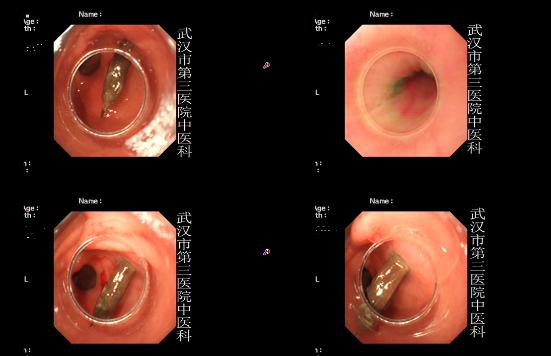

据权威专家介绍,胃穿孔的可怕之处在于穿孔后大量的胃液会流入腹腔,引起细菌性或者化学性腹膜炎等症状,如不及时抢救会危及生命。没有发生腹膜炎的小穿孔及空腹穿孔,可采用保守疗法。一般禁食,放置鼻胃管抽吸胃内容物,以及输液补充水和微量元素,应用抗菌药物预防腹腔感染即可。而饱餐后穿孔,常伴随着弥漫性腹膜炎,需在六到十二小时内进行急诊手术。另外,慢性穿孔发展严重时,也需要进行外科手术治疗。

胃穿孔的患者除了感到上腹部剧烈疼痛外,恶心、休克、发热等也是它的常见症状,有部分病人还会伴有腹胀等问题。如果你想判断自己是否得了胃穿孔,可以通过以下方法进行检查:

2.用X线检查,尤其是立位腹平片,通常可以发现膈下是否有游离气体。

3.用B超,CT检查等。